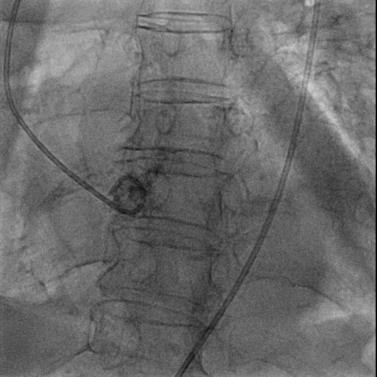

22mm球囊预扩张

置入纽脉医疗29mm球囊扩张式PrizValve